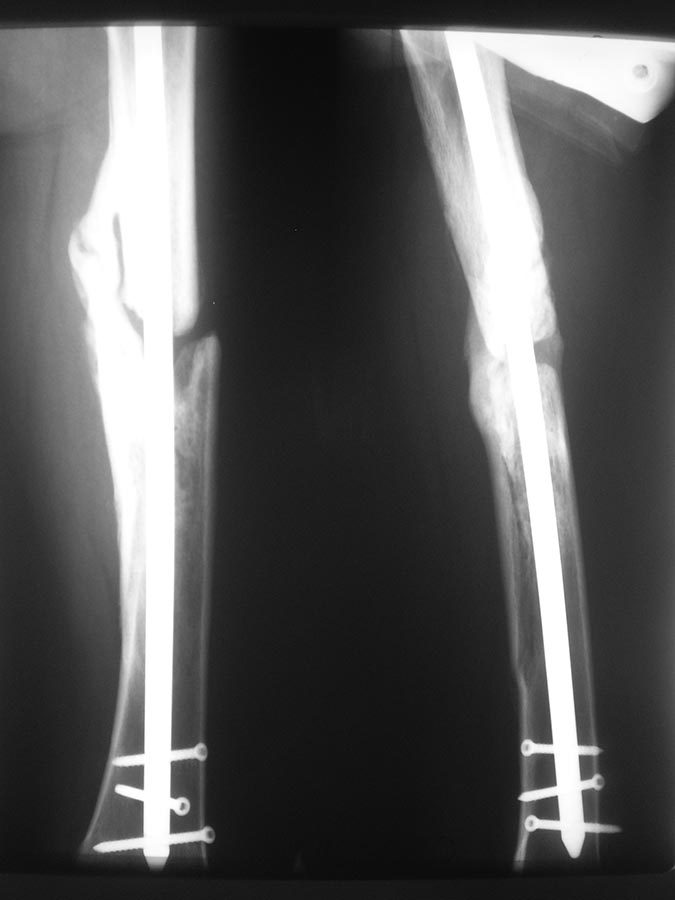

Добрый день уважаемые коллеги. Вашему вниманию представляю пациента(мужчина, 30 лет). Тяжелая сочетанная травма 7 мес. назад. Из скелетной травмы: открытый перелом бедра, открытый перелом дистального метаэпифиза левого плеча, закрытый перелом шейки левого плеча). Все повреждения были прооперированы. Бедро синтезировано штифтом Остеомед d-11мм. Раны зажили первично. Пациент после выписки впервые появился на контрольный осмотр ч/з 7 месяцев. Жалобы на боли в левом бедре при нагрузке, ощущение подвижности в месте перелома. Передвигается без дополнительных средств опоры. Локально: отека левого бедра нет, п/операционные рубцы без признаков воспаления. движения в суставах левой н/конечности в полном объеме, безболезненны.( все снимки, первичные, после операции и на сегодня прилагаю). основной вопрос, тактический, чем лучше выполнить реостеостеосинтез. У нас в наличии имеется: из штифтов Остеомед d-12мм, старый набор Синтез с канюлированными штифтами максимальный d-14мм., пластины LC-DCP, аппарат Илизарова. В плане 2 варианта: 1) удаление проксимальных блокирующих винтов(сломаный тоже), фиксация бедра спице-стержневым аппаратом из 2-х опор и компрессия в аппарате. 2)удаление металлоконструкции, и выполнение реостеосинтеза с рассверливанием( учитывая очень широкий канал) с установкой винтов поллеров в дистальном отломке. Жду ваших предложений и мнений. Спасибо заранее

С возросшей регулярностью на форуме обсуждаются «беспричинные» случаи несращения переломов после интерлокинга. В постах больше внимания уделяется обсуждению тактике дальнейшего лечения. Причём в подобных случаях предлагаемые варианты не отличаются многообразием и ограничиваются либо таким же остеосинтезом только стержнем большего диаметра, либо пластинкой с костной пластикой либо внеочаговой фиксацией. К сожалению, почти всегда остаются без анализа возможные причины, приведшие к несращению. А жаль. Ведь вероятность сращения после интерлокинга приближается к ста процентам, и точно установленная причина, почему это не произошло в положенные сроки, может подсказать тактику дальнейшего лечения. С моей точки зрения, безусловной причиной несращения перелома бедренной кости в обсуждаемой случае является оставшаяся подвижность между проксимальным и дистальными фрагментами после остеосинтеза. На это указывает и сам больной. Причём очаг нестабильности расположен в проксимальном костном фрагменте между ним и проксимальным концом стержня. Хотя на первый взгляд кажется, что вся проблема в дистальном костном отломке, точнее в отсутствии стабильности между ним и дистальным концом стержня из-за значительной разницы в диаметрах стержня и костномозгового канала. На последних рентгенограммах чётко видна костная мозоль между латеральным кортикальным слоем и стержнем на входе в костномозговой канал дистального отломка. Она говорит об эффективности дистального блокирования тремя блокирующими винтами в полифокальных плоскостях. И на сегодня биомеханическая система дистальный отломок – стержень работает как единое целое. Формируется новый костномозговой канал в дистальном отломке по ходу дистального конца стержня за счёт образования костной мозоли между латеральным кортикальным слоем и стержнем. И этот формирующийся костномозговой канал точно соответствует диаметру стержня, что является дополнительным фактором, стабилизирующим дистальный конец стержня. Поэтому, с моей точки зрения, не имеют смысла предложения, направленные на введение каких-либо металлоконструкций, уменьшающих размер костномозгового канала дистального отломка. Да и сделать это технически при такой рентгенологической картине крайне сложно, если вообще возможно. Что касается проксимального блокирования. Крайне неудачно проведен самый проксимальный блокирующий винт. Если авторы рассчитывали на последующую динамизацию (что, при таком переломе крайне неразумно), то его надо было проводить по верхнему краю овального отверстия. Если предполагалось статическая фиксация на протяжении всего периода сращения, то было бы разумнее его провести по нижнему краю овального отверстия. Тогда нагрузка при передвижении больного распределялась бы на оба проксимальных блокирующих винта, что снизило бы вероятность их перелома. Я уже писал в предыдущих постах с похожими случаями. Два блокирующих винта во фронтальной плоскости, один из которых проведен через овальное отверстие, не могут обеспечить стабильность во фронтальной плоскости, если костномозговой канал на выходе из проксимального отломка не соответствует диаметру стержня. И это, с моей точки зрения, служит наиболее частой причиной несращения. И это же служило причиной частых несращений при фиксации тонкими стержнями без рассверливания костномозгового канала. В данном случае мы бы рассверлили канал до диаметра канала на выходе из проксимального отломка (13-14 мм) и имплантировали бы стержень такого же диаметра как последнее сверло. Отдаю предпочтение протезированию всей длины бедренной кости с дистальным блокирование в мыщелках. Лучший вариант, с моей точки зрения, – реконструктивный стержень с проксимальным блокированием в шейке бедра двумя винтами. Хотя допустим и обычный стержень с расположением винта в овальном отверстии по его нижнему краю. Режим фиксации, безусловно, статический.

Непохоже. Вверху он нормально держался, и внизу центрального отломка канал неширокий. Подвижность явно была, но скорее всего, больше за счет расколотого и длинного периферического отломка, винты-то далеко, а рычаг длинный. В сочетании с неустранненным смещением по ширине, отсутствием кортикальной аппозиции по латеральной стенке даже достаточно активного костеобразования здесь не хватило, чтобы стабилизировать отломки.